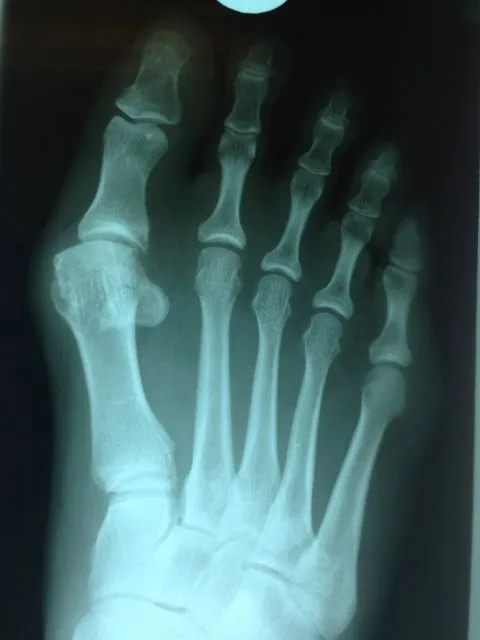

Pre and Postop Xrays

In the x-ray image below is a Hallux Valgus or what is more commonly known as a bunion deformity where the great toe is deviated towards the lesser toes causing abnormal structure which is a result of genetics, abnormal shoegear and abnormal mechanics will cause wearing of the joint and enlargement of the head of the long bone called the first metatarsal.

Post-surgical repair of the same patient bunion deformity with the great toe now in rectus (straight) position with surgically placed screws in the head of the first metatarsal that were used to secure fixation of the cut made across the bone to translate the head of the bone laterally in order to reduce the deformity. The screws will remain in place even after the bone heals.